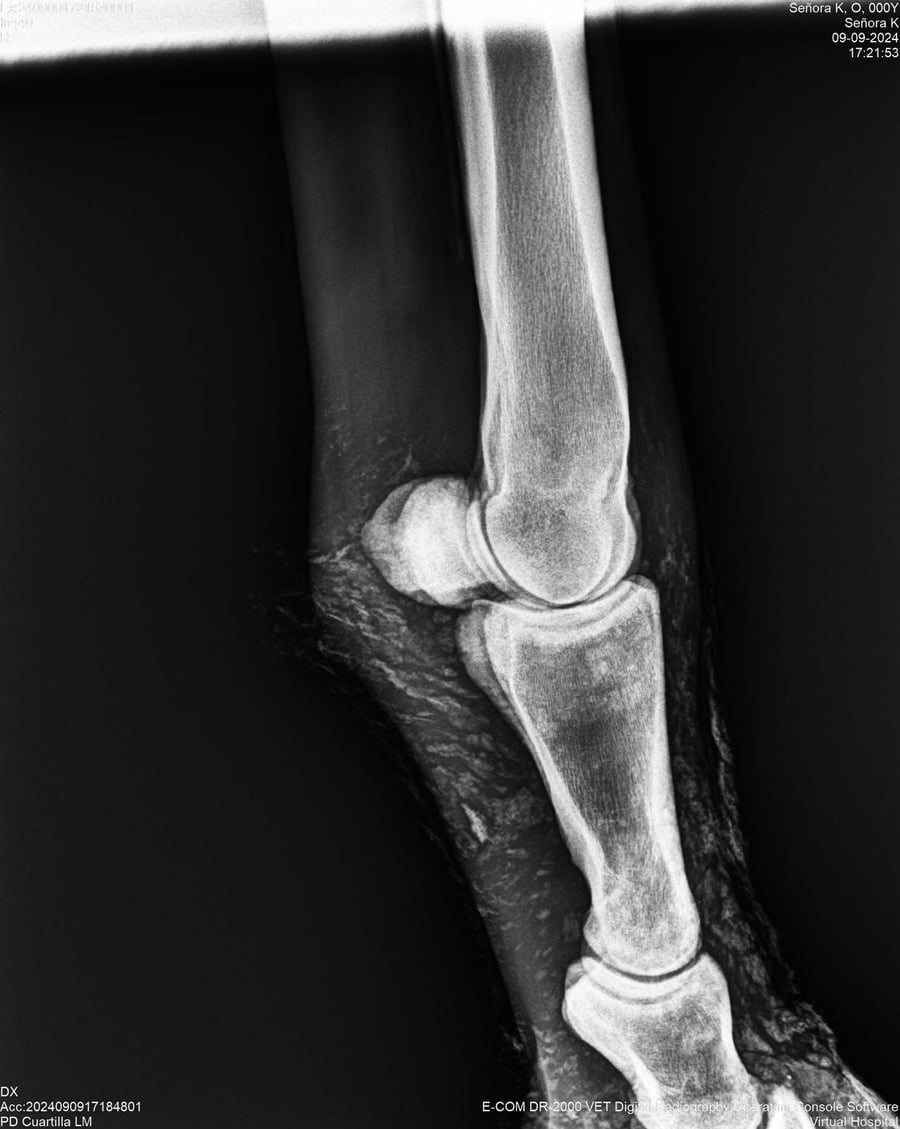

LOTE 44, SEÑORA K

Identificador: #291147-

Generacion 2022